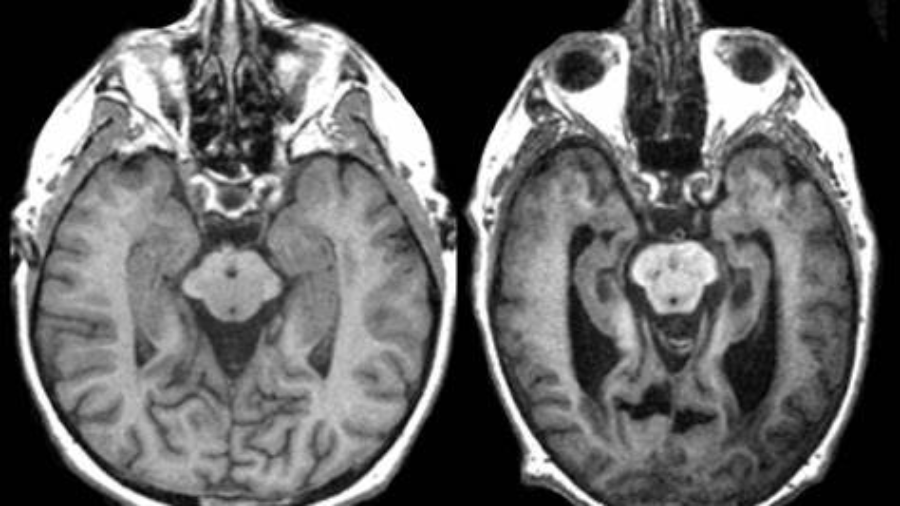

En primer lugar debemos entender qué es el Alzheimer, es un trastorno cerebral que afecta la memoria principalmente, el pensamiento y el llevar a cabo tareas sencillas de la cotidianidad; no es un proceso que se da en la vejez sino que es un daño complejo que causa grandes cambios en el cerebro de quienes padecen esta enfermedad. Estas alteraciones aparecen mucho antes de que se presenten los primeros síntomas y se estima que cerca de seis millones de personas en los Estados Unidos viven con este trastorno.